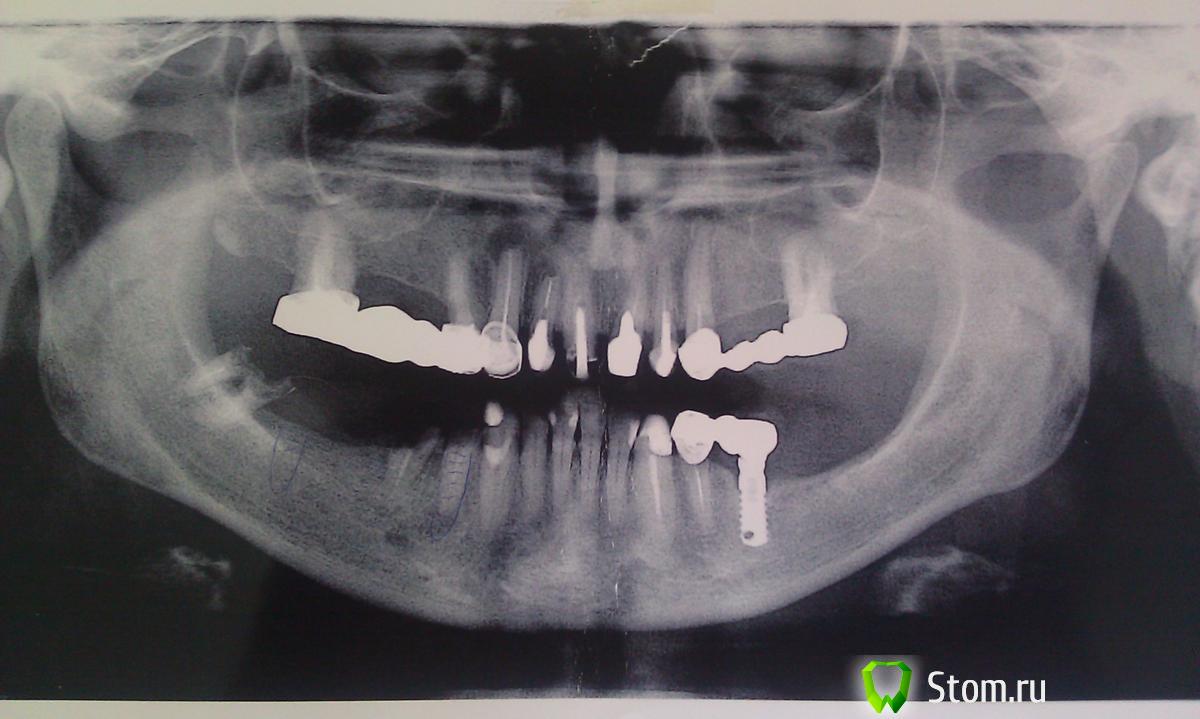

Eugen Опубликовано 27 февраля, 2012 Поделиться Опубликовано 27 февраля, 2012 Добрый день. Подскажите пожалуйста, что это за система. Со слов пациентки ставили 18 лет назд, (был мост 34- 36, где 34 - свой зуб, 36 имплант, коронка была на винтовой фиксации ). Планирую 34-36 - мост, используя старый имплант. Извините, если создал уже похожую тему или написал не там.... Ссылка на комментарий

Eugen Опубликовано 12 марта, 2012 Автор Поделиться Опубликовано 12 марта, 2012 (изменено) я уже думал по поводу его удаления, но что потом? не понадобится ли костная пластика??? у пациентки нет денег, все по минимуму...... решаем проблемы по мере их поступления , а не все сразу ....общая картина на орто, К тому же ставит 8mm имплант ,по моему ,в обл 36 не очень хороший вариант. 34 уже нет (как писал ранее был перелом коронки из-за раскрутившегося винта на импланте), имплант будет в позиции 46 а не 47, 13 - трогать пока не хочет, со слов наблюдает уже лет 15 - после лечения, гранулема в размерах не меняется, зуб не беспокоит . верх трогать не хочет. Пациентке 62 года. Изменено 12 марта, 2012 пользователем Eugen Ссылка на комментарий